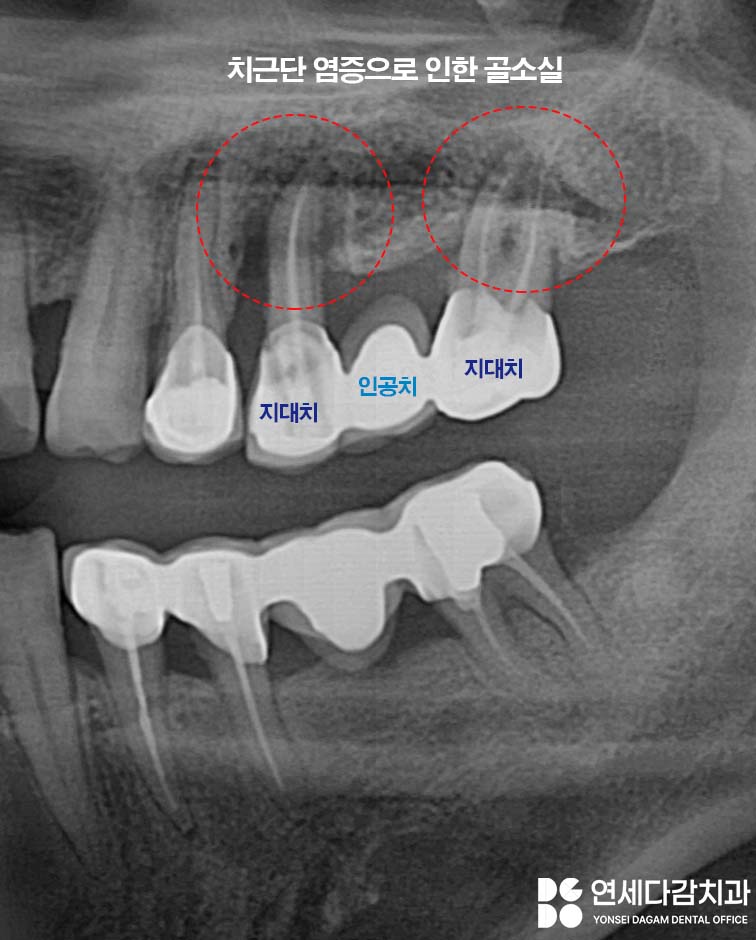

브릿지를 지탱하는 치아,

즉 지대치 주변에 문제가

생겼을 가능성이 큽니다.

그런데 지대치 주변 잇몸뼈가

염증으로 인해 녹아내리기 시작하면

브릿지 부위 전체가 흔들리게 됩니다.